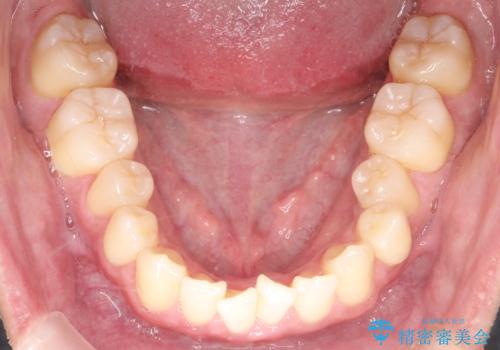

- 前歯のガタガタを主訴に来院されました。

上下の前歯のガタガタと左上の歯が反対にかんでいる状態でした。

上下の歯と歯の間をわずかに削り並べる計画としました。

目立たずに歯並びがよくなり、前歯に装着されたセラミックも壊さずに矯正治療が終了し満足していただけました。